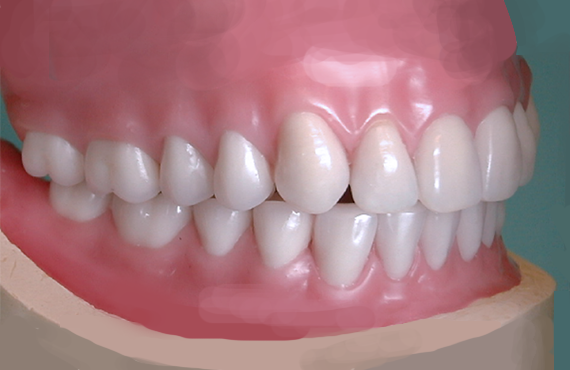

Implants in the Aesthetic Zone

With advances in implantology and our understanding of biology, biomechanics and restorative solutions, expectations from out patients and ourselves are at the highest they have ever been. This lecture will discuss implant placement, hard and soft tissue requirements,...

Immediate Dentures. The Complete Process – The Basis for any Full Arch Restoration

An Immediate Denture is the first prosthesis made for a patient with total extraction and rehabilitation of a dental arch, whether the final prosthesis is any Removable or Fixed Restoration.A properly planned and executed Immediate Denture, not only...